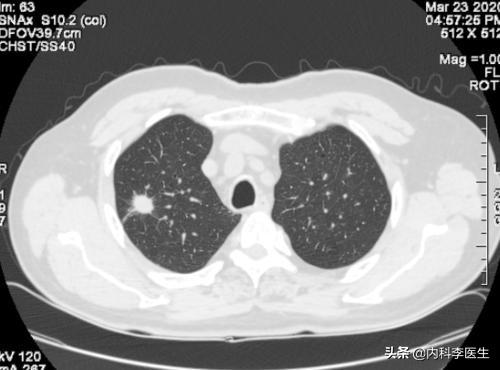

健康診断への意識が高まるにつれ、肺結節が発見される人が増えている。肺結節とは画像診断の用語で、肺結節の画像上の定義は、肺実質に完全に囲まれた、境界明瞭な小さな病変(直径≤30mm).結節の形態は、固結または亜固結に分類される。亜固結はさらに、純粋なすりガラス結節と部分的な固結に分類される。直径30mmを超える病変は結節ではなく腫瘤であり、悪性の可能性が高い。

ほとんどの肺結節は薬を飲んでも治らない経口抗炎症薬で吸収できる炎症性結節はごくわずかである。肺結節の臨床管理は結節の形状と大きさに基づいて行われ、さまざまな管理計画が立てられる。 一般に、ほとんどの結節は3ヵ月、6ヵ月、9ヵ月、1年(結節の形状と大きさによる)の定期的な経過観察が推奨される。ごく少数の結節で、明らかな悪性の特徴を有するものは、外科的切除が考慮される。